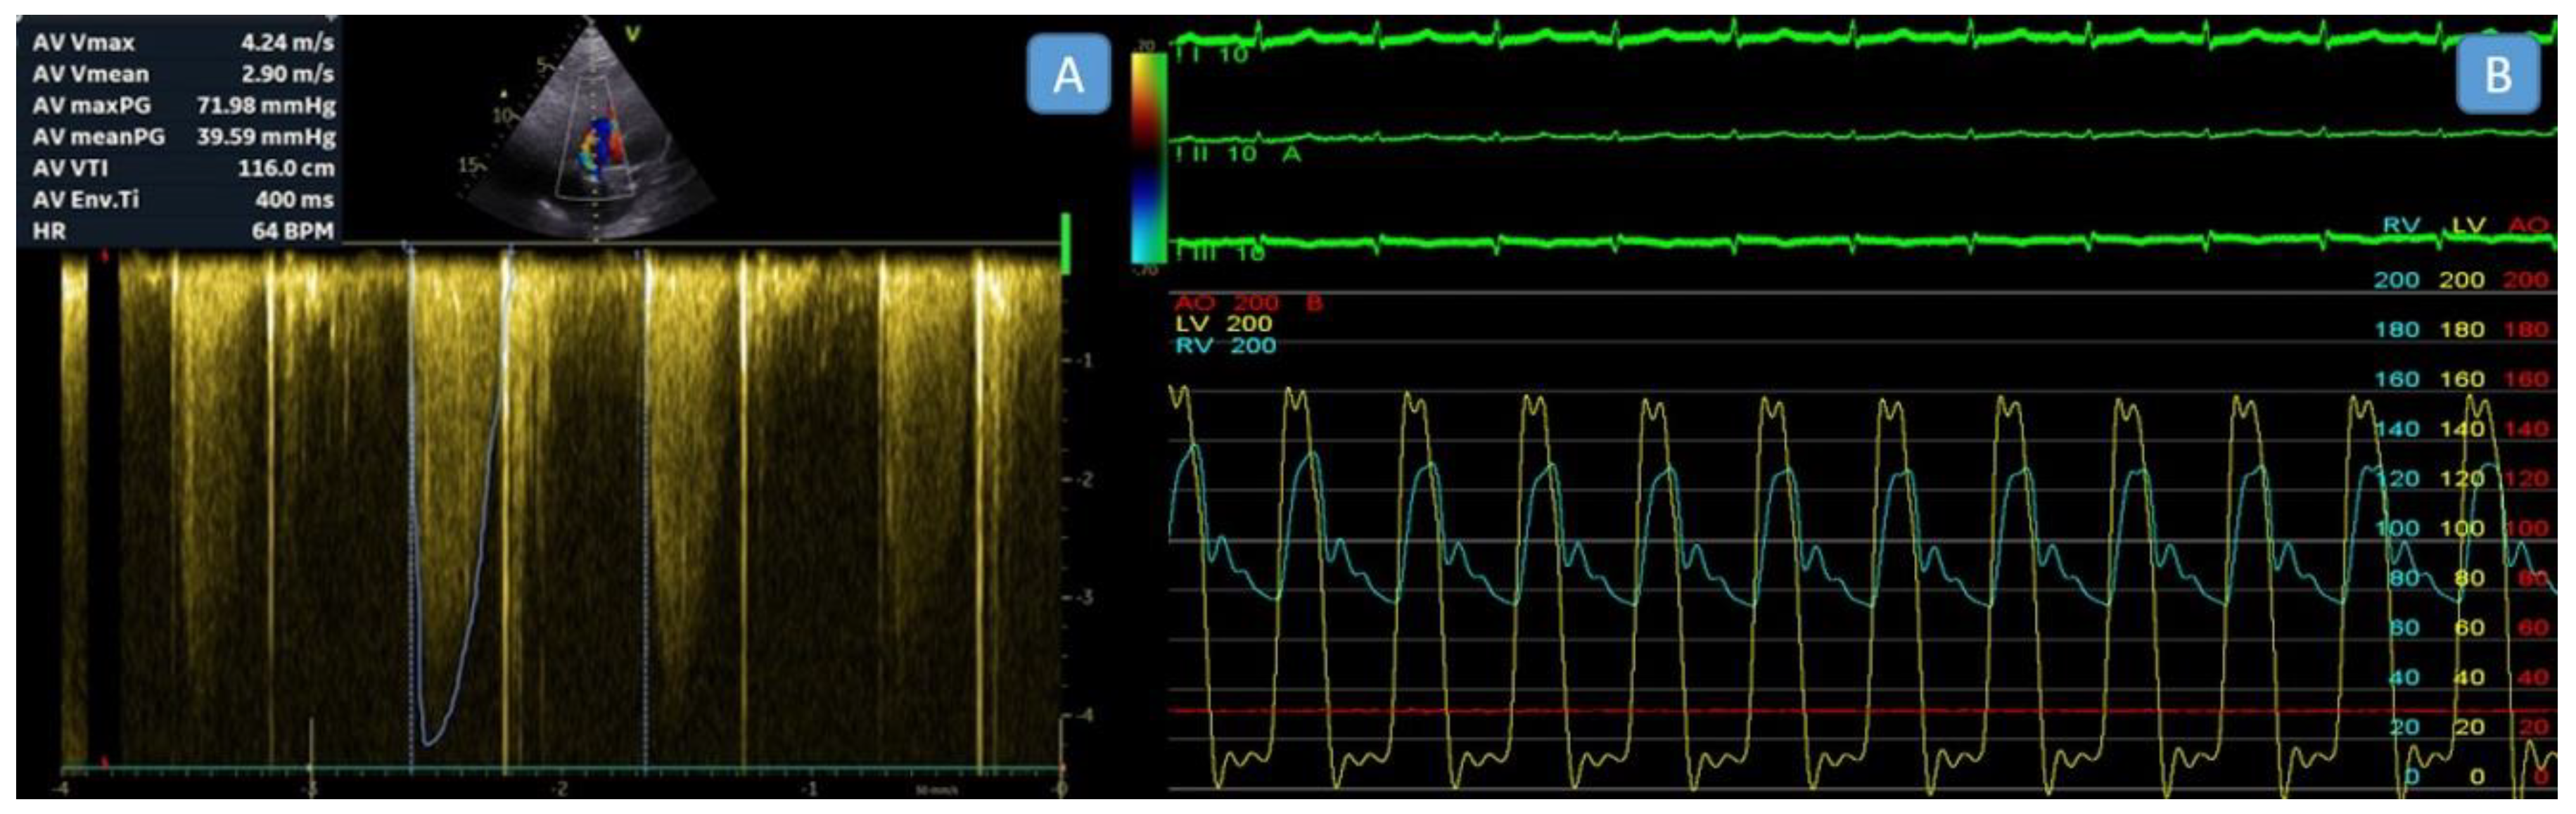

The peak velocity, mean gradient, velocity time integral (VTI), Doppler velocity index (DVI), and effective orifice area (EOA) of the aortic prosthetic valve were measured and recorded. The simplified Bernoulli equation was employed to calculate pressure gradients across aortic prosthetic valves noninvasively. Peak aortic velocity and mean aortic gradients were derived from the flow envelope, using the highest velocity recorded from multiple imaging views. The mean gradient was obtained by tracing the Doppler envelope (Figure 1A).

The procedures were performed under conscious or deep sedation, ensuring patient comfort and procedural safety. For all patients, invasive hemodynamic measurements were obtained using a dual-catheter technique that allows for simultaneous recording of left ventricular (LV) and aortic pressures to assess TVG accurately. Two venous sheaths were placed in the femoral vein, and one arterial sheath was inserted into the femoral artery. A pigtail catheter was then positioned in the aortic root via the arterial sheath, and a diagnostic coronary sinus (CS) catheter was advanced into the CS through one of the venous sheaths to serve as markers for transseptal puncture. Using these markers as guidance, a transseptal puncture was performed employing the modified Brockenbrough technique under fluoroscopy visualization. After a successful puncture, a pigtail catheter was advanced into the left atrium and then across the mitral valve into the left ventricle (LV) (Video 1). This setup allowed for the simultaneous recording of left ventricular and aortic pressures, enabling accurate calculation of “peak-to-peak” transvalvular pressure gradients (Figure 1B). During the procedure, fluoroscopy was used to guide catheter placement and evaluate the motion and function of the prosthetic aortic valve leaflets, ensuring their proper operation during hemodynamic assessment. The dual-catheter approach is especially beneficial for patients with mechanical aortic valves, as it avoids crossing the valve apparatus, reducing the complication risk. Numerous studies have validated this method for its accuracy and reliability in measuring transvalvular pressure gradients, establishing it as a standard practice in invasive hemodynamic assessments (10,11).

Figure 1. A. Measurement of the gradient across the aortic mechanical valve by transthoracic echocardiography. B. Simultaneous invasive measurement of aortic and left ventricular pressure gradients. The yellow line represents left ventricular pressure, and the blue line represents aortic pressure. In this patient, who had a surgical aortic valve replacement, transthoracic echocardiography indicated a pressure gradient of 59/38 mmHg across the aortic valve, while the invasive peak-to-peak gradient measurement was 19 mmHg.